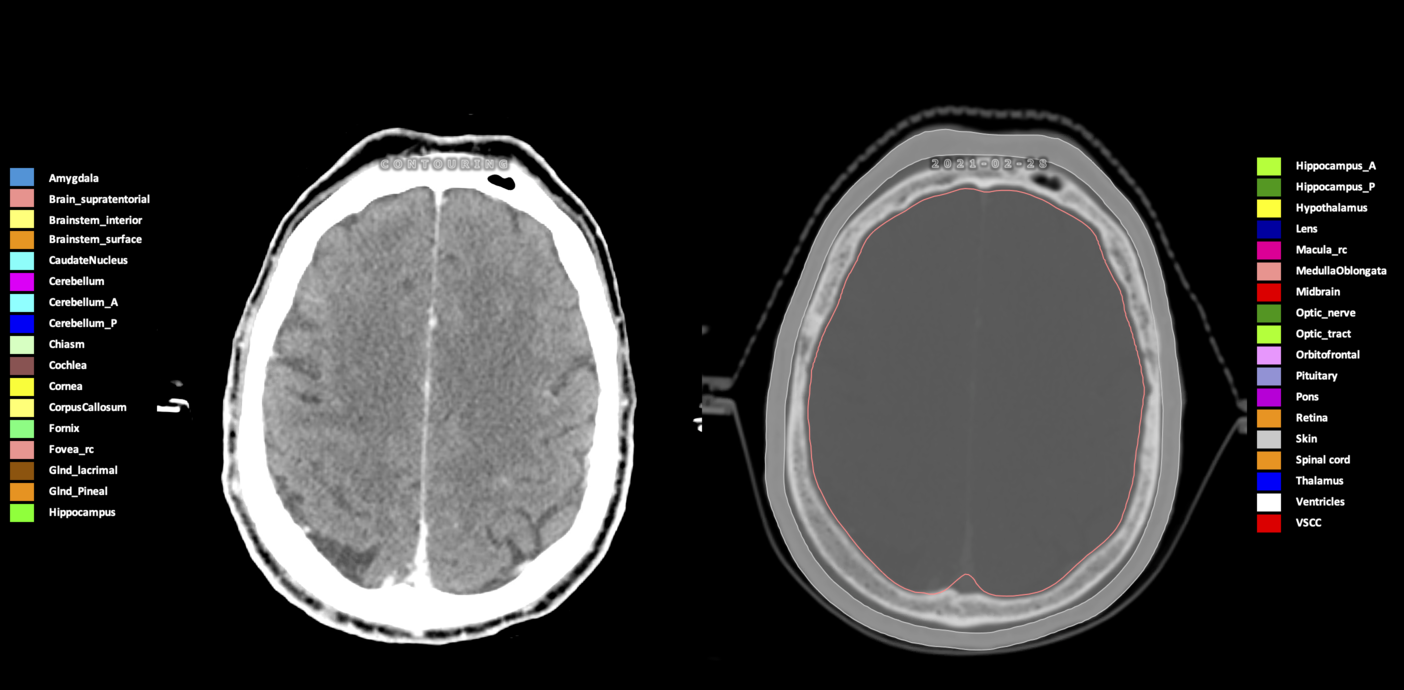

Included are all OARs known to be relevant for radiation-induced toxicity in neuro-oncology: brain, brainstem (midbrain, pons, medulla oblongata), chiasm, cerebellum (anterior & posterior), cochlea, cornea, hippocampus (anterior & posterior), hypothalamus, lens, lacrimal gland, optic nerve, pituitary, skin, and vestibular & semicircular canals. To further facilitate research on cognition, vision and radiological changes after irradiation of the brain, potential clinically-relevant OARs are included: amygdala, caudate nucleus, cerebellum (anterior & posterior), corpus callosum, fornix, macula, optic tract, orbitofrontal cortex, periventricular space (PVS), pineal gland, and thalamus.

Three-dimensional delineation of the 25 consensus OARs for neuro-oncology are shown on CT (WW/WL 120/40, 3000/600), 3T MR images, (T1Gd, T2FLAIR 1mm) and 7T MR (MP2RAGE 0.7 mm). All are presented in transversal, sagittal and coronal view.